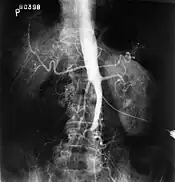

Fluoroscopic image of an aorta affected by Leriche's syndrome

The physical examination usually shows weakened femoral pulses and a reduced ankle-brachial index. The diagnosis can be verified by color duplex scanning, which reveals either a peak systolic velocity ratio ≥2.5 at the site of stenosis and/or a monophasic waveform. MRA and multidetector CTA are often used to determine the extent and type of obstruction. Another technique is digital subtraction angiography which allows verification of the diagnosis and endovascular treatment in a single session.[1]

Angiography provides important information regarding the perfusion and patency of distal arteries (e.g. femoral artery). The presence of collateral arteries in the pelvic and groin area is important in maintaining crucial blood flow and lower limb viability. However, angiography should only be used if symptoms warrant surgical intervention.[1]